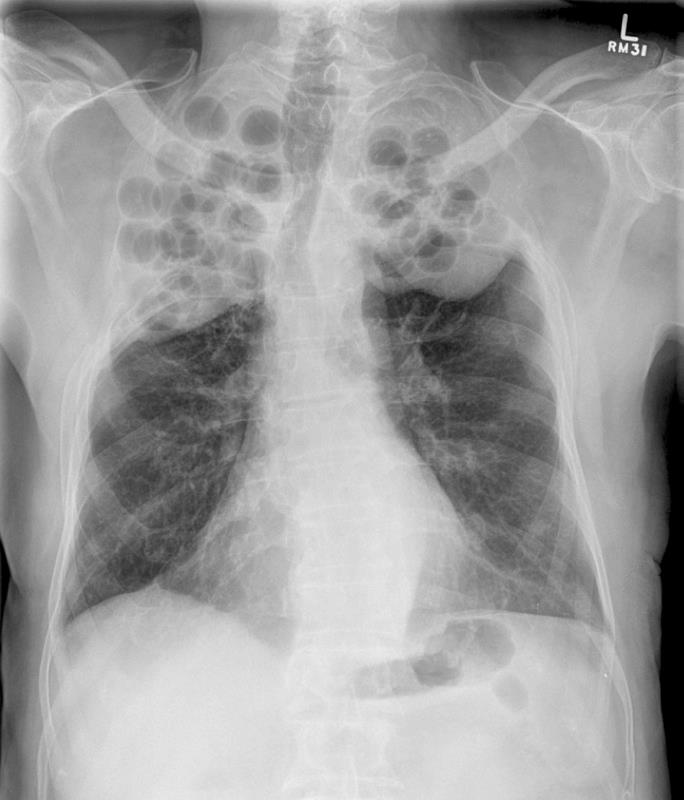

Interpret this X-ray